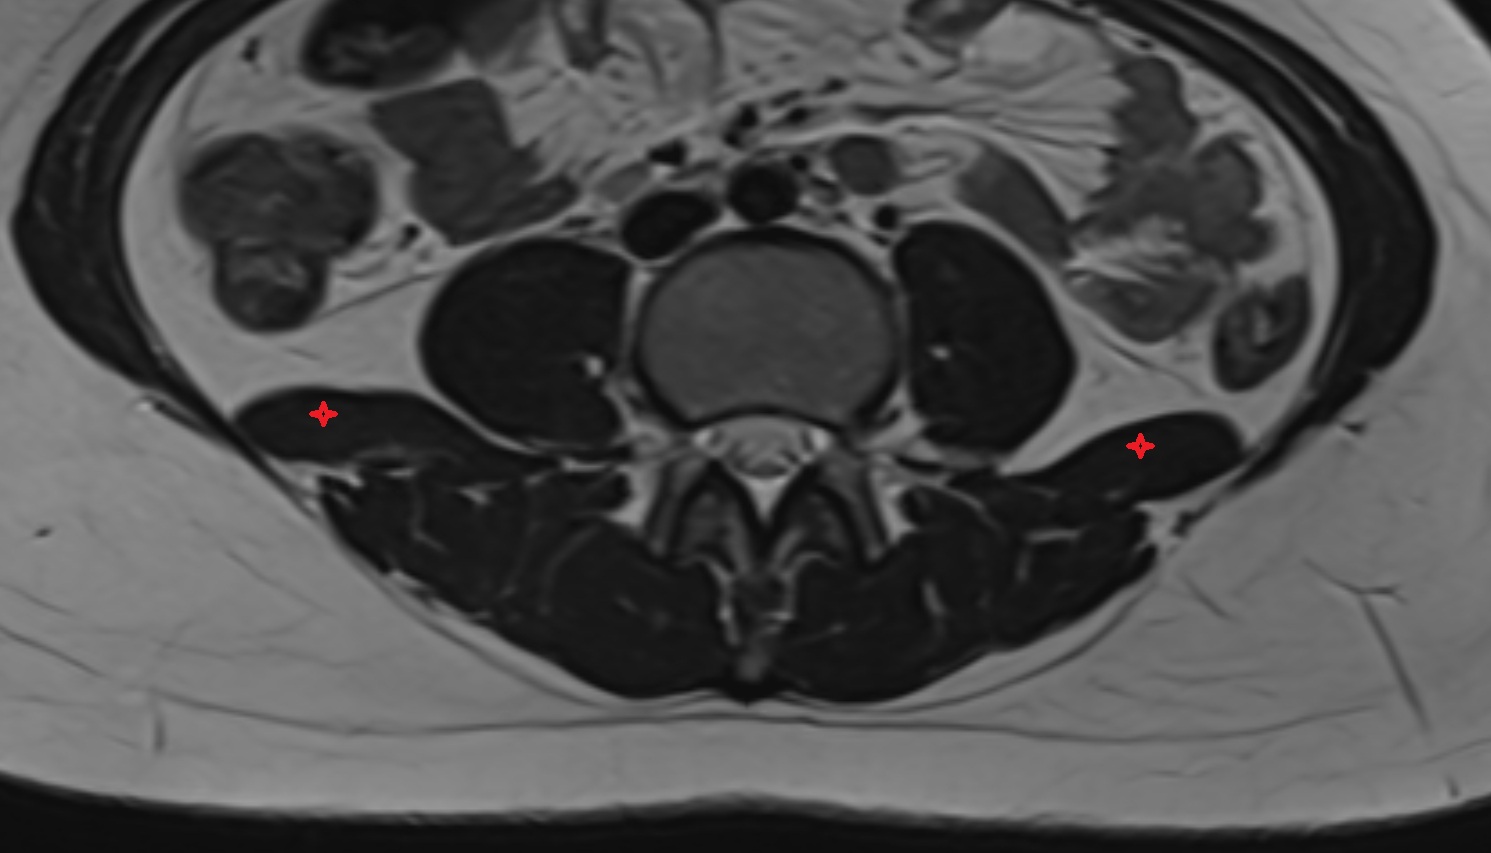

- Psoas major muscle

- Quadratus lumborum muscle

- Cauda equina